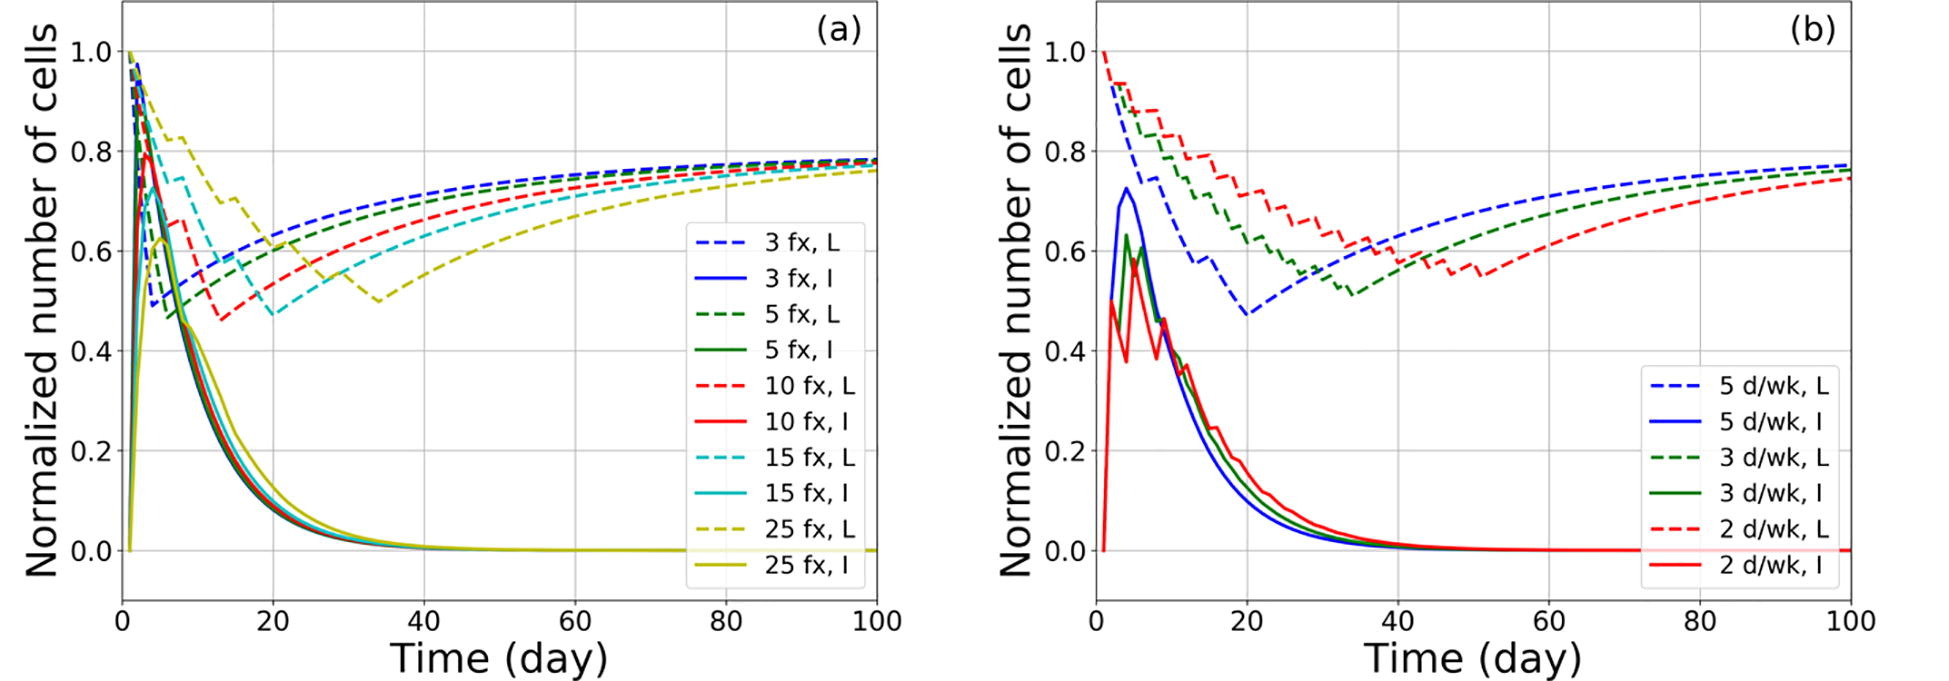

The impact of radiation therapy on the immune system has recently gained attention particularly when delivered in combination with immunotherapy. However, it is unclear how different treatment fractionation regimens influence the interaction between the immune system and radiation. The goal of this work was to develop a mathematical model that quantifies both the immune stimulating as well as the immunosuppressive effects of radiotherapy and simulates the effects of different fractionation regimens based on patient data.

The framework describes the temporal evolution of tumor cells, lymphocytes, and inactivated dying tumor cells releasing antigens during radiation therapy, specifically modeling how recruited lymphocytes inhibit tumor progression. The parameters of the model were partly taken from the literature and in part extracted from blood samples (circulating lymphocytes: CLs) collected from hepatocellular carcinoma patients undergoing radiotherapy and their outcomes. The dose volume histograms to circulating lymphocytes were calculated with a probability-based model.

Based on the fitted parameters, the model enabled a study into the depletion and recovery of CLs in patients as a function of fractionation regimen. Our results quantify the ability of short fractionation regimens to lead to shorter periods of lymphocyte depletion and predict faster recovery after the end of treatment. The model shows that treatment breaks between fractions can prolong the period of lymphocyte depletion and should be avoided.